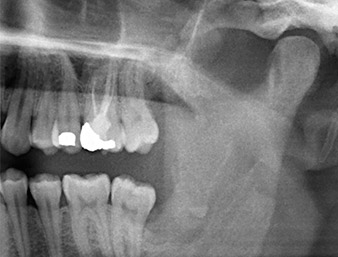

A 26-year old patient had recurring pain in the operative area six months after osteotomy of tooth 38 (LL8) and complained of hyposensitivity in the area innervated by the inferior alveolar nerve. He was referred by the referring dentist, who had not performed the original tooth extraction himself, to the Department of Oral Surgery at the University Dental Clinic Vienna.

The root remnant in the region of tooth 38 (LL8) was already displaying close proximity to the inferior alveolar nerve on the OPG. The root had fractured during the osteotomy but had not been removed by the primary treatment provider due to intraoperative pain. To ensure as little trauma as possible to the tissue, the new osteotomy was to be carried out using a piezo surgical system. The patient had an unremarkable medical history and was a non-smoker.

OPG 6 months after osteotomy

Fig. 1: OPG 6 months after osteotomy of tooth 38 (LL8): radix relicta lies close to the inferior alveolar nerve.

It could be seen in the 3D image (digital volume tomography) that the root remnant was located disto-caudally in the transition from the horizontal to the ascending portion of the mandible (Fig. 2).

Based on his medical history, our patient (non-smoker, 26 years old) had a very good chance of a successful outcome. Due to indication of the root remnant’s close proximity to the inferior alveolar nerve on the OPG, digital volume tomography was used in addition (6).